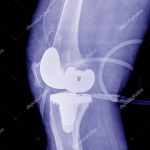

Recovery after Knee Joint Knee Replacement Surgery

About 10 years ago a Joint Knee Replacement Surgery meant at least 7 days of hospitalization. Now a days hospital stay is restricted to 48 to 73 hours and the operated patients are sent home with instructions. Your surgeon will let you know when it’s best to leave the hospital. This is based on the results of the surgery and your condition. He gives clear discharge instructions. Back at home there are a few diehards in ensuring quick and proper recovery. In India more than 50% of operated patients do not enjoy 100% benefit of Joint Knee Replacement as they did not focus on their recovery. They complain about incomplete range motion and pain. Some of the common problems encountered by a patient recovering in Home settings which come in the way of full recovery from Joint Knee Replacement Surgeries are given below-